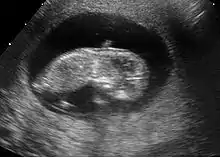

Échographie au premier trimestre de la grossesse

L'échographie au premier trimestre de la grossesse est un temps primordial de la surveillance de la grossesse. Seule l'échographie permet de répondre aux quatre questions principales en début de grossesse :

L'aspect échographique du tout début de grossesse

- Le premier signe échographique d'une grossesse est la visualisation d'un sac ovulaire. Il est visible entre 4 semaines et 1 jour et 4 semaines et 3 jours; Il mesure alors 2 à 3 mm. L'utilisation de la voie endovaginale est souvent nécessaire pour le voir. Le sac ovulaire a l'aspect d'une petite tache noire, excentrée par rapport à la cavité utérine, correspondant à la cavité chorionique entourée d'une couronne d'échogénéicité forte : le trophoblaste.